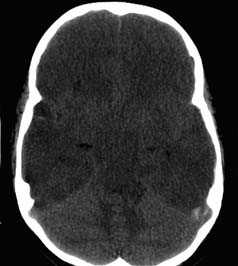

КТ-картина диффузного аксонального поражения мозга характеризуется увеличением объема мозга, в результате которого под сдавлением находятся боковые и III желудочки, субарахноидальные конвекситальные пространства, а также цистерны основания мозга. Нередко выявляют наличие мелкоочаговых геморрагий в белом веществе полушарий мозга, мозолистом теле, подкорковых и стволовых структурах.

Для диффузного аксонального повреждения головного мозга типично длительное коматозное состояние после черепно-мозговой травмы, а также ярко выраженные стволовые симптомы. Коме сопутствует симметричная либо асимметричная децеребрация или декортикация как спонтанными, так и легко провоцируемыми раздражениями (например, болевыми). Изменения мышечного тонуса весьма вариабельны (горметония или диффузная гипотония). Типично проявление пирамидно-экстрапирамидных парезов конечностей, в том числе асимметричные тетрапарезы.

Кроме грубых нарушений ритма и частоты дыхания проявляются и вегетативные расстройства: повышение температуры тела и артериального давления, гипергидроз и др. Характерной особенностью клинического течения диффузного аксонального повреждения мозга является трансформация состояния пациента из продолжительной комы в транзиторное вегетативное состояние. О наступлении такого состояния свидетельствует спонтанное открывание глаз (при этом отсутствуют признаки слежения и фиксации взора).